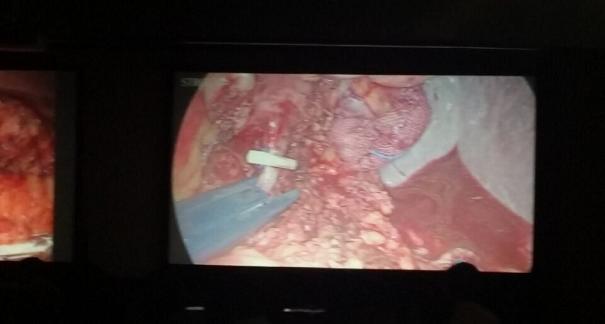

2015年10月23-25日,河北省醫(yī)學(xué)會(huì)肝膽外科學(xué)術(shù)年會(huì)在河北省石家莊市頤園賓館隆重召開(kāi)。本次學(xué)術(shù)會(huì)議河北省醫(yī)學(xué)會(huì)特邀了北京301總院的胡明根教授、天津第一中心醫(yī)院的張雅敏教授、山西醫(yī)大醫(yī)院的趙浩亮、河北醫(yī)科大學(xué)第二醫(yī)院劉建華教授等國(guó)內(nèi)知名專家參會(huì)。參加會(huì)議的醫(yī)院達(dá)100余家,近300名肝膽外科的臨床專家和一線醫(yī)生們親臨會(huì)場(chǎng),在此進(jìn)行廣泛的學(xué)術(shù)交流。25號(hào)全天會(huì)議安排了五臺(tái)手術(shù)視頻演示,全體參會(huì)人員進(jìn)行觀摩,并實(shí)時(shí)提問(wèn),進(jìn)行手術(shù)交流。演示手術(shù)包括腹腔鏡胰、十二指腸切除術(shù)、腹腔鏡左、右半肝切除術(shù)、腹腔鏡門脈高壓癥的治療、兩鏡或三鏡聯(lián)合膽石癥的治療、開(kāi)腹胰、十二指腸切除術(shù)、手術(shù)演示中多次使用了我公司產(chǎn)品速豐(可吸收止血結(jié)扎夾),產(chǎn)品使用滿意度受到專家們的一致好評(píng)。